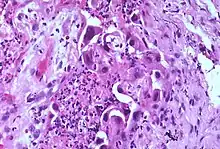

Marked atypia of type 2 pneumocytes is a characteristic finding in association with treatment with busulfan and other chemotherapeutic agents.